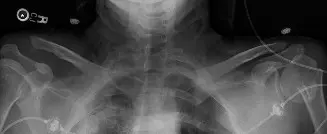

تشخيص إصابات مفصل الترقوة الأخرمي تصنيف روكوود

يُعد التشخيص الدقيق لإصابات مفصل الترقوة الأخرمي هو الخطوة الأولى نحو العلاج الفعال. يعتمد الأستاذ الدكتور محمد هطيف على تقييم شامل يشمل الفحص السريري الدقيق والتصوير الطبي، مسترشدًا بنظام تصنيف روكوود (Rockwood Classification) الذي يُعد المعيار الذهبي لتحديد شدة الإصابة وتوجيه القرارات العلاجية.

التقييم قبل الجراحة والتصوير التشخيصي

التقييم الإشعاعي (التصوير):

الصور الشعاعية القياسية (الأشعة السينية):

تُعد ضرورية لتقييم المفصل. تشمل:

- المنظر الأمامي الخلفي (AP View): للكتف (AP حقيقي مع إمالة ذنبية 30° أو منظر غراشي) ومنظر جانبي إبطي (لتقييم الإزاحة الأمامية الخلفية واستبعاد خلع كسري خلفي للمفصل الحقاني العضدي)، ومنظر Y للكتف.

- منظر زانكا (Zanca View): وهو منظر AP متخصص مع إمالة رأسية 10-15°، يتركز على مفصل الترقوة الأخرمي، مما يقلل من تداخل العظام من الأخرم وشوكة لوح الكتف، ويوفر رؤية أوضح لمساحة مفصل الترقوة الأخرمي.

- صور الإجهاد (Stress Views): كانت تُستخدم تاريخيًا (صور AP ثنائية الجانب مع حمل المريض أوزانًا تتراوح من 10-15 رطلاً في كل يد) للتمييز بين إصابات النوع الثاني والثالث من خلال إبراز الإزاحة الرأسية. ومع ذلك، فقد انخفض استخدامها بسبب مخاوف تتعلق بانزعاج المريض، والنتائج غير المتسقة، والتعرض للإشعاع. غالبًا ما يكون الفحص السريري والصور القياسية كافيين.